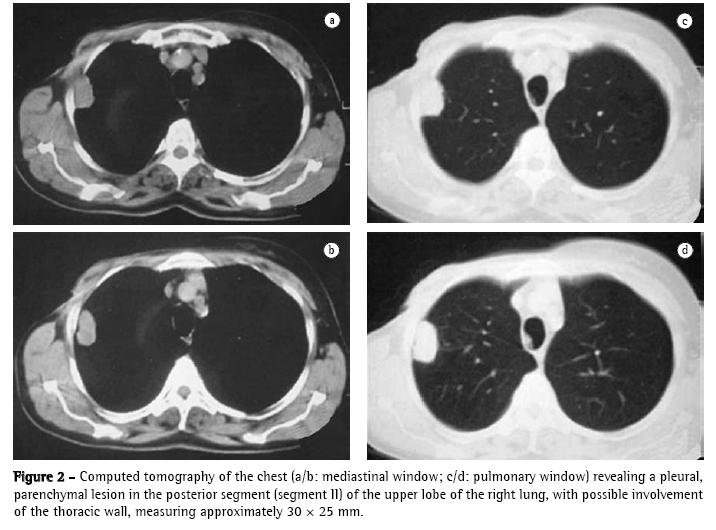

The patient then underwent computed tomography of the chest, which revealed a pleural, parenchymal pulmonary nodule measuring approximately 30 × 25 mm (Figure 2) in the right lung. Therefore, a hypothetical diagnosis of pulmonary metastasis of the breast carcinoma previously removed was made, and biopsy was indicated for diagnostic confirmation.

The anatomopathological examination revealed that it was a non-capsulated, regular lesion measuring 30 × 25 mm and presenting a firm and fibroelastic consistency. Microscopy (Figure 3) revealed vessels, adipose tissue, cartilage, well-differentiated (but disorganized) bronchial structures, and highly vascularized fibrovascular stroma with interposed embryonic bronchi, compatible with pulmonary hamartoma.